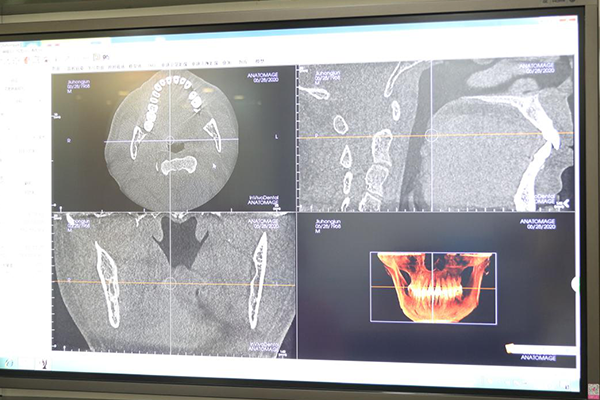

“麦芽博士种牙专家团在接诊我后,综合考虑我的个人情况,为我量身定制了个性化种牙解决方案。”在谈到为何选择麦芽口腔进行种植牙手术,刘洪军面带满意的微笑,“本来以为要种好几颗牙的,医生的方案设计只需要种上一颗功能牙,就可以恢复正常咀嚼,当时听完方案我的第一感觉就是麦芽很靠谱,真的是为我们患者着想,不让你花多一分冤枉钱!”麦芽博士种牙团专家表示,刘洪军种的是左下3区第6号功能牙,我们采取数字化精确种植技术,导航定位将植体安放在最恰当的位置,这颗牙就足够行使全部后牙区咀嚼功能,种上后可以防止其他牙齿的继续松动、缺失。

在经过一系列精确的数字化CBCT影像检测后,刘洪军的数字化精确种植牙手术进行得十分顺利。“种牙前我没有什么好担心的,麦芽的医生和护士都很专业,服务也十分热情,进行的每一步操作都有明确详细的说明,手术中我也没有任何感觉,很快就种好了。”种完牙的刘洪军一脸轻松:“种牙其实不贵,但要选对。以后我的种植牙都交给麦芽了!大品牌、大专家、种牙有保障,放心更暖心。”